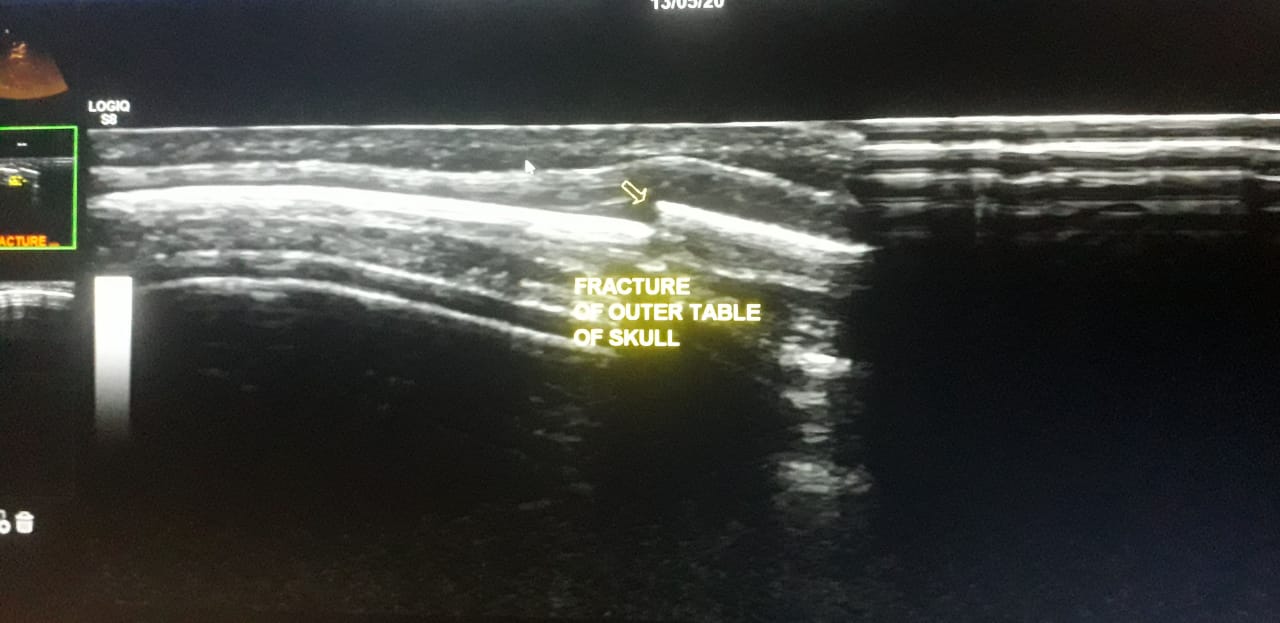

Ultrasound image of fracture of skull

(musculoskeletal ultrasound) :fracture of the outer table of skull on ultrasound…